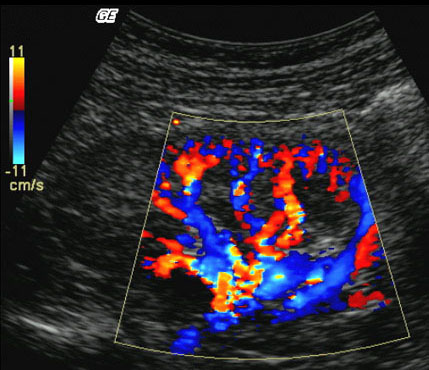

Another taxonomic scheme for ultrasound visualization is based on the different types of data the technique utilized. 3D Freehand and 4D ultrasound, pose very different challenges compared to 2D ultrasound or when handling multiple modalities. Blending b-mode ultrasound for tissue and color-doppler ultrasound for blood flow can be challenging enough in 2D if not in 3D. An example image is shown in Figure 1d. In addition to the ultrasound input, the combination of other medical imaging modalities, such as CT or MRI with ultrasound, provide more information, but also more challenges to the visualization researcher.

Visual presentation of the data is the last stage of the pipeline before the user. The basic B–mode ultrasound images can be depicted on a screen in a straight-forward manner as varying pixel intensities according to the echo amplitude. Doppler information can be included as well with color-encoded blood-flow direction. Other data, such as tissue strain can also be included into 2D as overlays. Another example of overlays is the CycleStack Plot which superimposes the respiratory signal onto a selected feature of interest in the ultrasound image lee10 . Doctors use this information to account for the respiration-caused motion of the tumor in order to minimize the damage done by certain tumor treatments.

For direct volume rendering, transfer functions map ultrasound data, i.e., voxel echogenicity in B–mode imaging, and frequency information in Doppler imaging, onto colors and opacities. Usually, this mapping is based on look-up tables. In color Doppler imaging the commonly used red-to-blue color transfer function encodes direction and velocity of flow, whereas a variety of predefined color maps is in use for B–mode volume rendering. Custom color map editors are available, but hardly ever used. Overall, there is a well-established set of color-maps used in clinical practice.

Multi-modal rendering is meant to bring two or more data-sets of the same object, into a single image. Having two or more datasets in the same scene creates a challenge to keep the cluttering of less interesting regions to a minimum from the datasets. For ultrasound, 3D Doppler data can be acquired simultaneously with 3D B–mode data. Jones et al. discuss several approaches to explore and visualize 4-D Doppler data jones03 . Multi-planar rendering, showing several slices at once, surface fitting of the Doppler data based on YCbCr color scheme values to improve separation between Doppler data and B–mode data. An approach is presented to blend multi-planar slice rendering into a DVR scene. The DVR is shown very transparent and the slices provide better detail along the perspective. A different way of combining B–mode with Doppler data was presented by Petersch and Hönigmann petersch07 . They propose a one level composite rendering approach allowing for blending flow and tissue information arbitrarily. Using silhouette rendering for the B–Mode and a mix of Phong shaded DVR and silhouette rendering on color Doppler.

A new technique for blending Doppler and B–mode was introduce by Yoo et al. yoo07 . Instead of blending two 2D rendered images (post fusion), or a blending the two volumes while rendering (composite fusion), it proposes a way to do both called progressive fusion (PGF). Post fusion has a problem with depth blending and composite fusion will get a too early ray termination. PGF compensate for this by using an if-clause to adjust the alpha-out value in the ray-caster to either the Doppler-signal or the B–mode-signal.